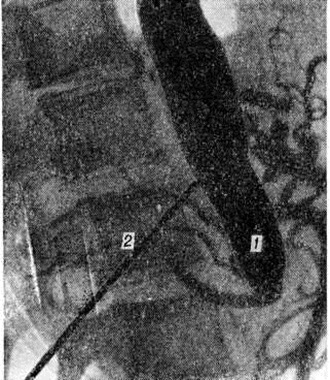

Топическую картину поражения можно установить пробой изотопной и рентгеноконтрастной ангиографии. Изотопная ангиография (смотри полный свод знаний) осуществляется пробой внутривенного введения технеция 99-м. Из методов рентгеноконтрастного исследования предпочтение следует отдать транслюмбальной пункционной аортографии (смотри полный свод знаний), при которой возможно получить изображение не только аорты, но и дистального сосудистого русла конечностей. Именно аортография выявляет локализацию и протяжённость поражения (рисунок 4—6), однако её следует проводить только при решении вопроса об оперативном лечении больного.